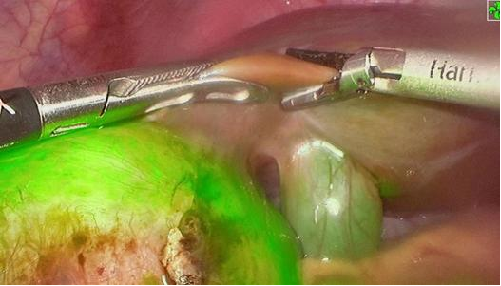

PL002是浙江普利药业有限公司研发的荧光/磁共振双模态造影剂,荧光/磁共振双模态造影剂的成功研发将成为提高脑胶质瘤手术效率的有效方案。术中荧光技术与核磁共振成像的结合,相较于单独使用,能够更准确地识别肿瘤组织与功能区的位置关系,以及患者的肿瘤浸润边缘。

PL002相较于吲哚菁绿具有明显优势。目前吲哚菁绿在临床使用中存在给药到手术时间不确定的问题,可能造成病灶与正常组织对比度不足,影响术中的病灶的判断,PL002采用独特的钆络合物与荧光分子共价键结合的分子结构设计,这种设计能够让医生在术前通过磁共振成像确定造影剂在病灶中的聚集情况,进而针对患者个体情况来对手术时间进行规划。同时,由于PL002体内更为稳定,在荷瘤小鼠模型中同等条件下荧光成像效果维持时间长于现有荧光造影剂,也保证了其在临床应用中具有更宽的手术窗口。

使用双模态造影剂可以为手术医生提供更加丰富的诊断信息,降低术中的决策压力,避免过度切成,增加发现微小病灶的可能性,最终实现患者的全面获益。此外,相较于传统荧光造影剂,PL002的安全性更高、体内更为稳定,成像效果更佳,为其临床使用提供了有效的支持。